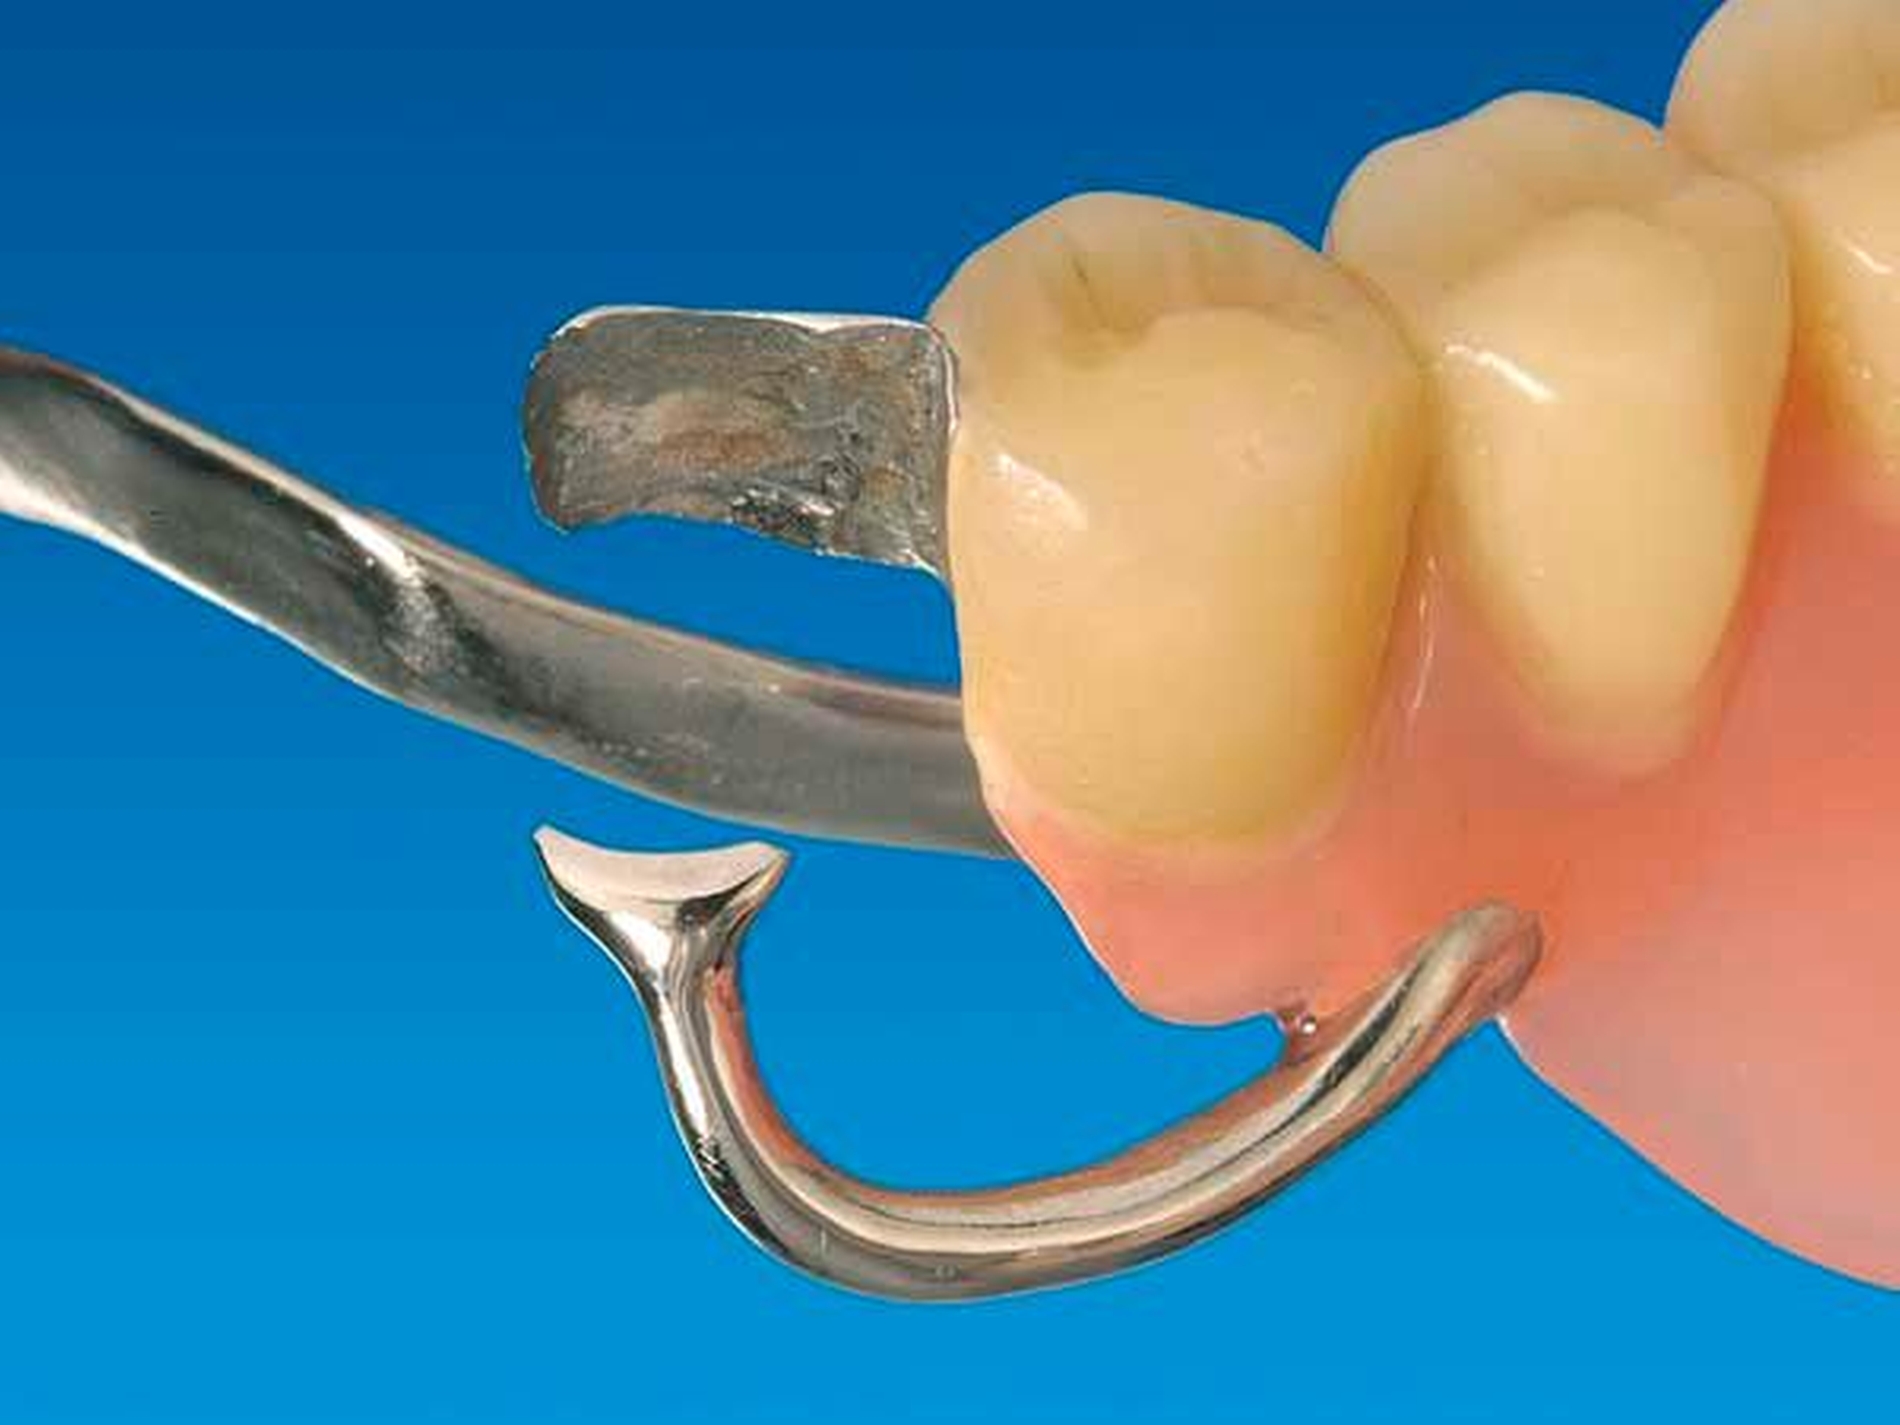

Die proximale Platte der RPI-Klammer blockiert wirkungsvoll dislozierende Sattelbewegungen (Abbildung 5), der von gingival inserierende Retentionsarm ist nahezu unsichtbar. Aufgrund des langen Federweges ist der Retentionsarm praktisch ermüdungsfrei und lässt sich gegebenenfalls leicht aktivieren. Die Abstützung liegt sattelfern analog einer Back-Action-Klammer. Für die RPI-Klammer wird am Ankerzahn neben der üblichen mesialen Klammerauflage die disto-approximale Wand parallel zur Einschubrichtung im Schmelz präpariert (Abbildung 6). Die Präparation sollte mindestens 1 mm oberhalb der Papille enden. Die präparierte Fläche dient der flächigen Anlage der proximalen Platte (Abbildung 3).